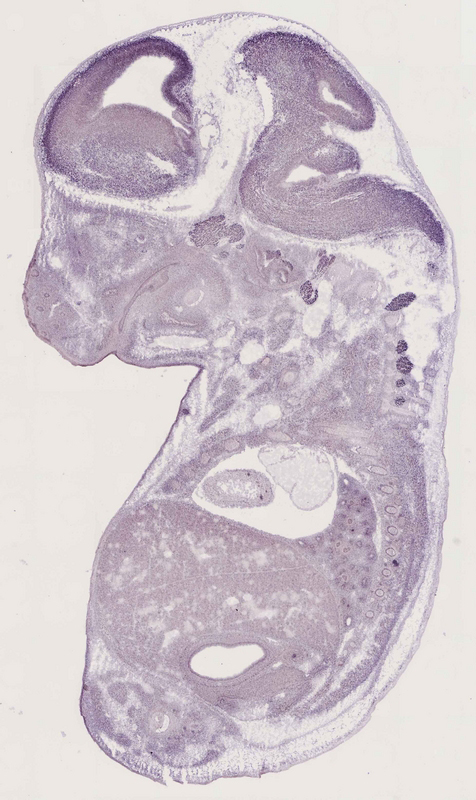

Specimen

euxassay_013785_03:

embryonic day 14.5

euxassay_013785_04: